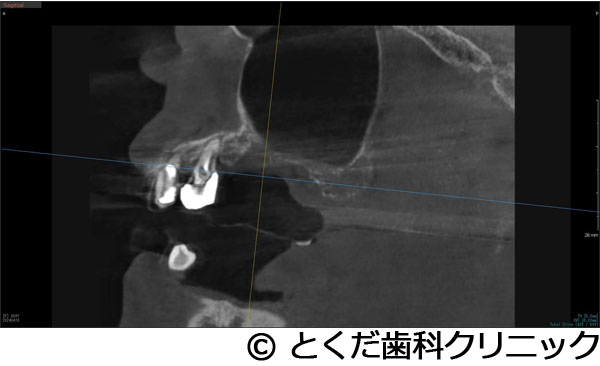

¡Ú¾ÉÎã4¡Ûº¸¾å4È֤ϥ¤¥ó¥×¥é¥ó¥ÈÈ´»õ¨»þËäÆþ¡¢º¸¾å6È֤Ͼå³Ü´û¸¹ü1¡Á2mm¤Î¥±¡¼¥¹¤Ç¥°¥é¥Õ¥È¥ì¥¹¥µ¥¤¥Ê¥¹¥ê¥Õ¥È¤ò»Ü¹Ô º¸²¼56¤Ï·ç»¤¬Â礤¯¡¢²¼³Ü¿À·Ð¤Þ¤Ç¤Îµ÷Î¥¤¬¤Ê¤¤¥±¡¼¥¹¤Ç¡¢²¼»õÁå´ÉËãáã¤ò²óÈò¤¹¤ë¤¿¤á¤Ë¥·¥ç¡¼¥È¥¤¥ó¥×¥é¥ó¥È¤ò»ÈÍÑ ºÇ½ªÊäÄÖʪ¤Ïº¸¾å456¤Î3¥æ¥Ë¥Ã¥È¤Î¥¸¥ë¥³¥Ë¥¢¥Ö¥ê¥Ã¥¸¡¢º¸²¼56¤Ï¥¸¥ë¥³¥Ë¥¢¤ÎÏ¢·ë´§¤òÁõÃ夷¤¿¥±¡¼¥¹

- º¸¾å4È֤ϥ¤¥ó¥×¥é¥ó¥ÈÈ´»õ¨»þËäÆþ¡¢º¸¾å6È֤Ͼå³Ü´û¸¹ü1¡Á2mm¤Î¥±¡¼¥¹¤Ç¥°¥é¥Õ¥È¥ì¥¹¥µ¥¤¥Ê¥¹¥ê¥Õ¥È¤ò»Ü¹Ô º¸²¼56¤Ï·ç»¤¬Â礤¯¡¢²¼³Ü¿À·Ð¤Þ¤Ç¤Îµ÷Î¥¤¬¤Ê¤¤¥±¡¼¥¹¤Ç¡¢²¼»õÁå´ÉËãáã¤ò²óÈò¤¹¤ë¤¿¤á¤Ë¥·¥ç¡¼¥È¥¤¥ó¥×¥é¥ó¥È¤ò»ÈÍÑ ºÇ½ªÊäÄÖʪ¤Ïº¸¾å456¤Î3¥æ¥Ë¥Ã¥È¤Î¥¸¥ë¥³¥Ë¥¢¥Ö¥ê¥Ã¥¸¡¢º¸²¼56¤Ï¥¸¥ë¥³¥Ë¥¢¤ÎÏ¢·ë´§¤òÁõÃ夷¤¿¥±¡¼¥¹

º¸²¼56¤Ï¡¢»õ¼þɤÇÂ礤ʹü·ç»¤òȼ¤Ã¤Æ¤¤¤¿¡£º¸¾å456¤Ë´Ø¤·¤Æ¤Ï¡¢Æ°Íɤ¬Â礤¯±ê¾É¤¬µ¯¤¡¢ÇÓÇ¿¤ª¤è¤Ó»õÀ¾å³Üƶ±ê¤òµ¯¤³¤·¤Æ¤¤¤¿¡£

´µ¼ÔÍͤϺ¸¾å¤ÎưÍɤ¬º¸¾å56¤ÎÈ´»õ¤ò´õ˾¡£¤½¤Î¸å¡¢¥¤¥ó¥×¥é¥ó¥È¼£ÎŤò´õ˾¤·¤¿¤¿¤áº¸¾å4¤Ë´Ø¤·¤Æ¤ÏÈ´»õ¨»þËäÆþ¡£º¸¾å6¤Ë´Ø¤·¤Æ¤Ï¡¢´û¸¹ü1¡Á2mm¤Ç¥¤¥ó¥×¥é¥ó¥È¼£ÎŤ¬¸·¤·¤¤¾õÂ֤Ǥ¢¤Ã¤¿¤¬¡¢¥°¥é¥Õ¥È¥ì¥¹¥µ¥¤¥Ê¥¹¥ê¥Õ¥È¤Ç¥¤¥ó¥×¥é¥ó¥ÈËäÆþ¤ò¹Ô¤¤¤Þ¤·¤¿¡£¤½¤Î¸å¡¢2¥õ·îȾ¸å¡¢ÂçÉý¤Ë¹ü¤¬·ç»¤·¤Æ¤¤¤ë²¼³Ü56¤ËÂФ·¤Æ¥·¥ç¡¼¥È¥¤¥ó¥×¥é¥ó¥È¤ò»ÈÍѤ·¤Æ¡¢²¼³Ü¿À·Ð¤Î»½ý¤òÈò¤±¤Æ¥¤¥ó¥×¥é¥ó¥ÈËäÆþ¤Î¼ê½Ñ¤ò½ª¤¨¤Æ¤¤¤Þ¤¹¡£¤½¤Î¸å2¥õ·î¸å¤Ë¸÷³Ø°õ¾Ý¤Ç°õ¾Ý¤ò¹Ô¤¤¡¢º¸¾å456¤Ï3¥æ¥Ë¥Ã¥È¤Î¥¸¥ë¥³¥Ë¥¢¥Ö¥ê¥Ã¥¸¤òÁõÃå¡£²¼º¸56¤Ë´Ø¤·¤Æ¤Ï¹ü·ç»¤¬Â礤¤¤¿¤á¡¢»õ´§Ä¹¤¬¤À¤¤¤ÖŤ¯¤Ê¤ë¤¿¤á¡¢¥¸¥ë¥³¥Ë¥¢¤ÎÏ¢·ë´§¤òÁõÃ夷¤Æ¼£ÎŤò½ª¤¨¤Æ¤¤¤Þ¤¹¡£

¾å³Ü6¤Ë´Ø¤·¤Æ¤Ï´û¸¹ü¤¬¾¯¤Ê¤¯¡¢¸·¤·¤¤¼£ÎŤǤϤ¢¤ê¤Þ¤·¤¿¤¬¡¢5¥õ·î¤Ç¼£ÎŤò½ª¤¨¡¢´µ¼ÔÍͤοÈÂÎŪ¡¢»þ´ÖŪ¡¢ÈñÍÑŪÉéô¤òºÇ¾®¸Â¤ËÍÞ¤¨¤ë¤³¤È¤¬¤Ç¤¤¿¤È¹Í¤¨¤Þ¤¹¡ÊÄ̾ï¤À¤È¼£ÎŤ¬ÉÔ²Äǽ¤È¸À¤ï¤ì¤ë¤³¤È¤¬Â¿¤¤¥±¡¼¥¹¤À¤È¹Í¤¨¤Þ¤¹¡£¤Ç¤¤¿¾ì¹ç¤â¡¢½¾Íè¤Î¥µ¥¤¥Ê¥¹¥ê¥Õ¥È¤ò¹Ô¤¤¡¢1ǯ°Ê¾å¤«1Ç¯ÄøÅ٤μ£ÎÅ´ü´Ö¤¬¤«¤«¤ë¤«¡¢»þ´ÖŪ¤ä¿ÈÂÎŪ¤Ë¤â¡¢¤Þ¤¿¡¢ÈñÍÑÌ̤ˤª¤¤¤Æ¤â¡¢´µ¼ÔÍͤËÉéô¤ò¤«¤±¤ë¥±¡¼¥¹¤À¤È¹Í¤¨¤Þ¤¹¡Ë¡£¤Þ¤¿¡¢²¼³Ü¤Ï¹ü·ç»¤¬Â礤¯¡¢²¼»õÁå´É¤Ø¤Î±Æ¶Á¤¬¹Í¤¨¤é¤ì¤ë¥ê¥¹¥¯¤¬¹Í¤¨¤é¤ì¤ë¥±¡¼¥¹¤Ç¤·¤¿¤¬¡¢¥·¥ç¡¼¥È¥¤¥ó¥×¥é¥ó¥È¤ò»ÈÍѤ¹¤ë¤³¤È¤Ç°ÂÁ´¤Ë¼£ÎŤò½ª¤¨¤ë¤³¤È¤¬¤Ç¤¤Þ¤·¤¿¡£